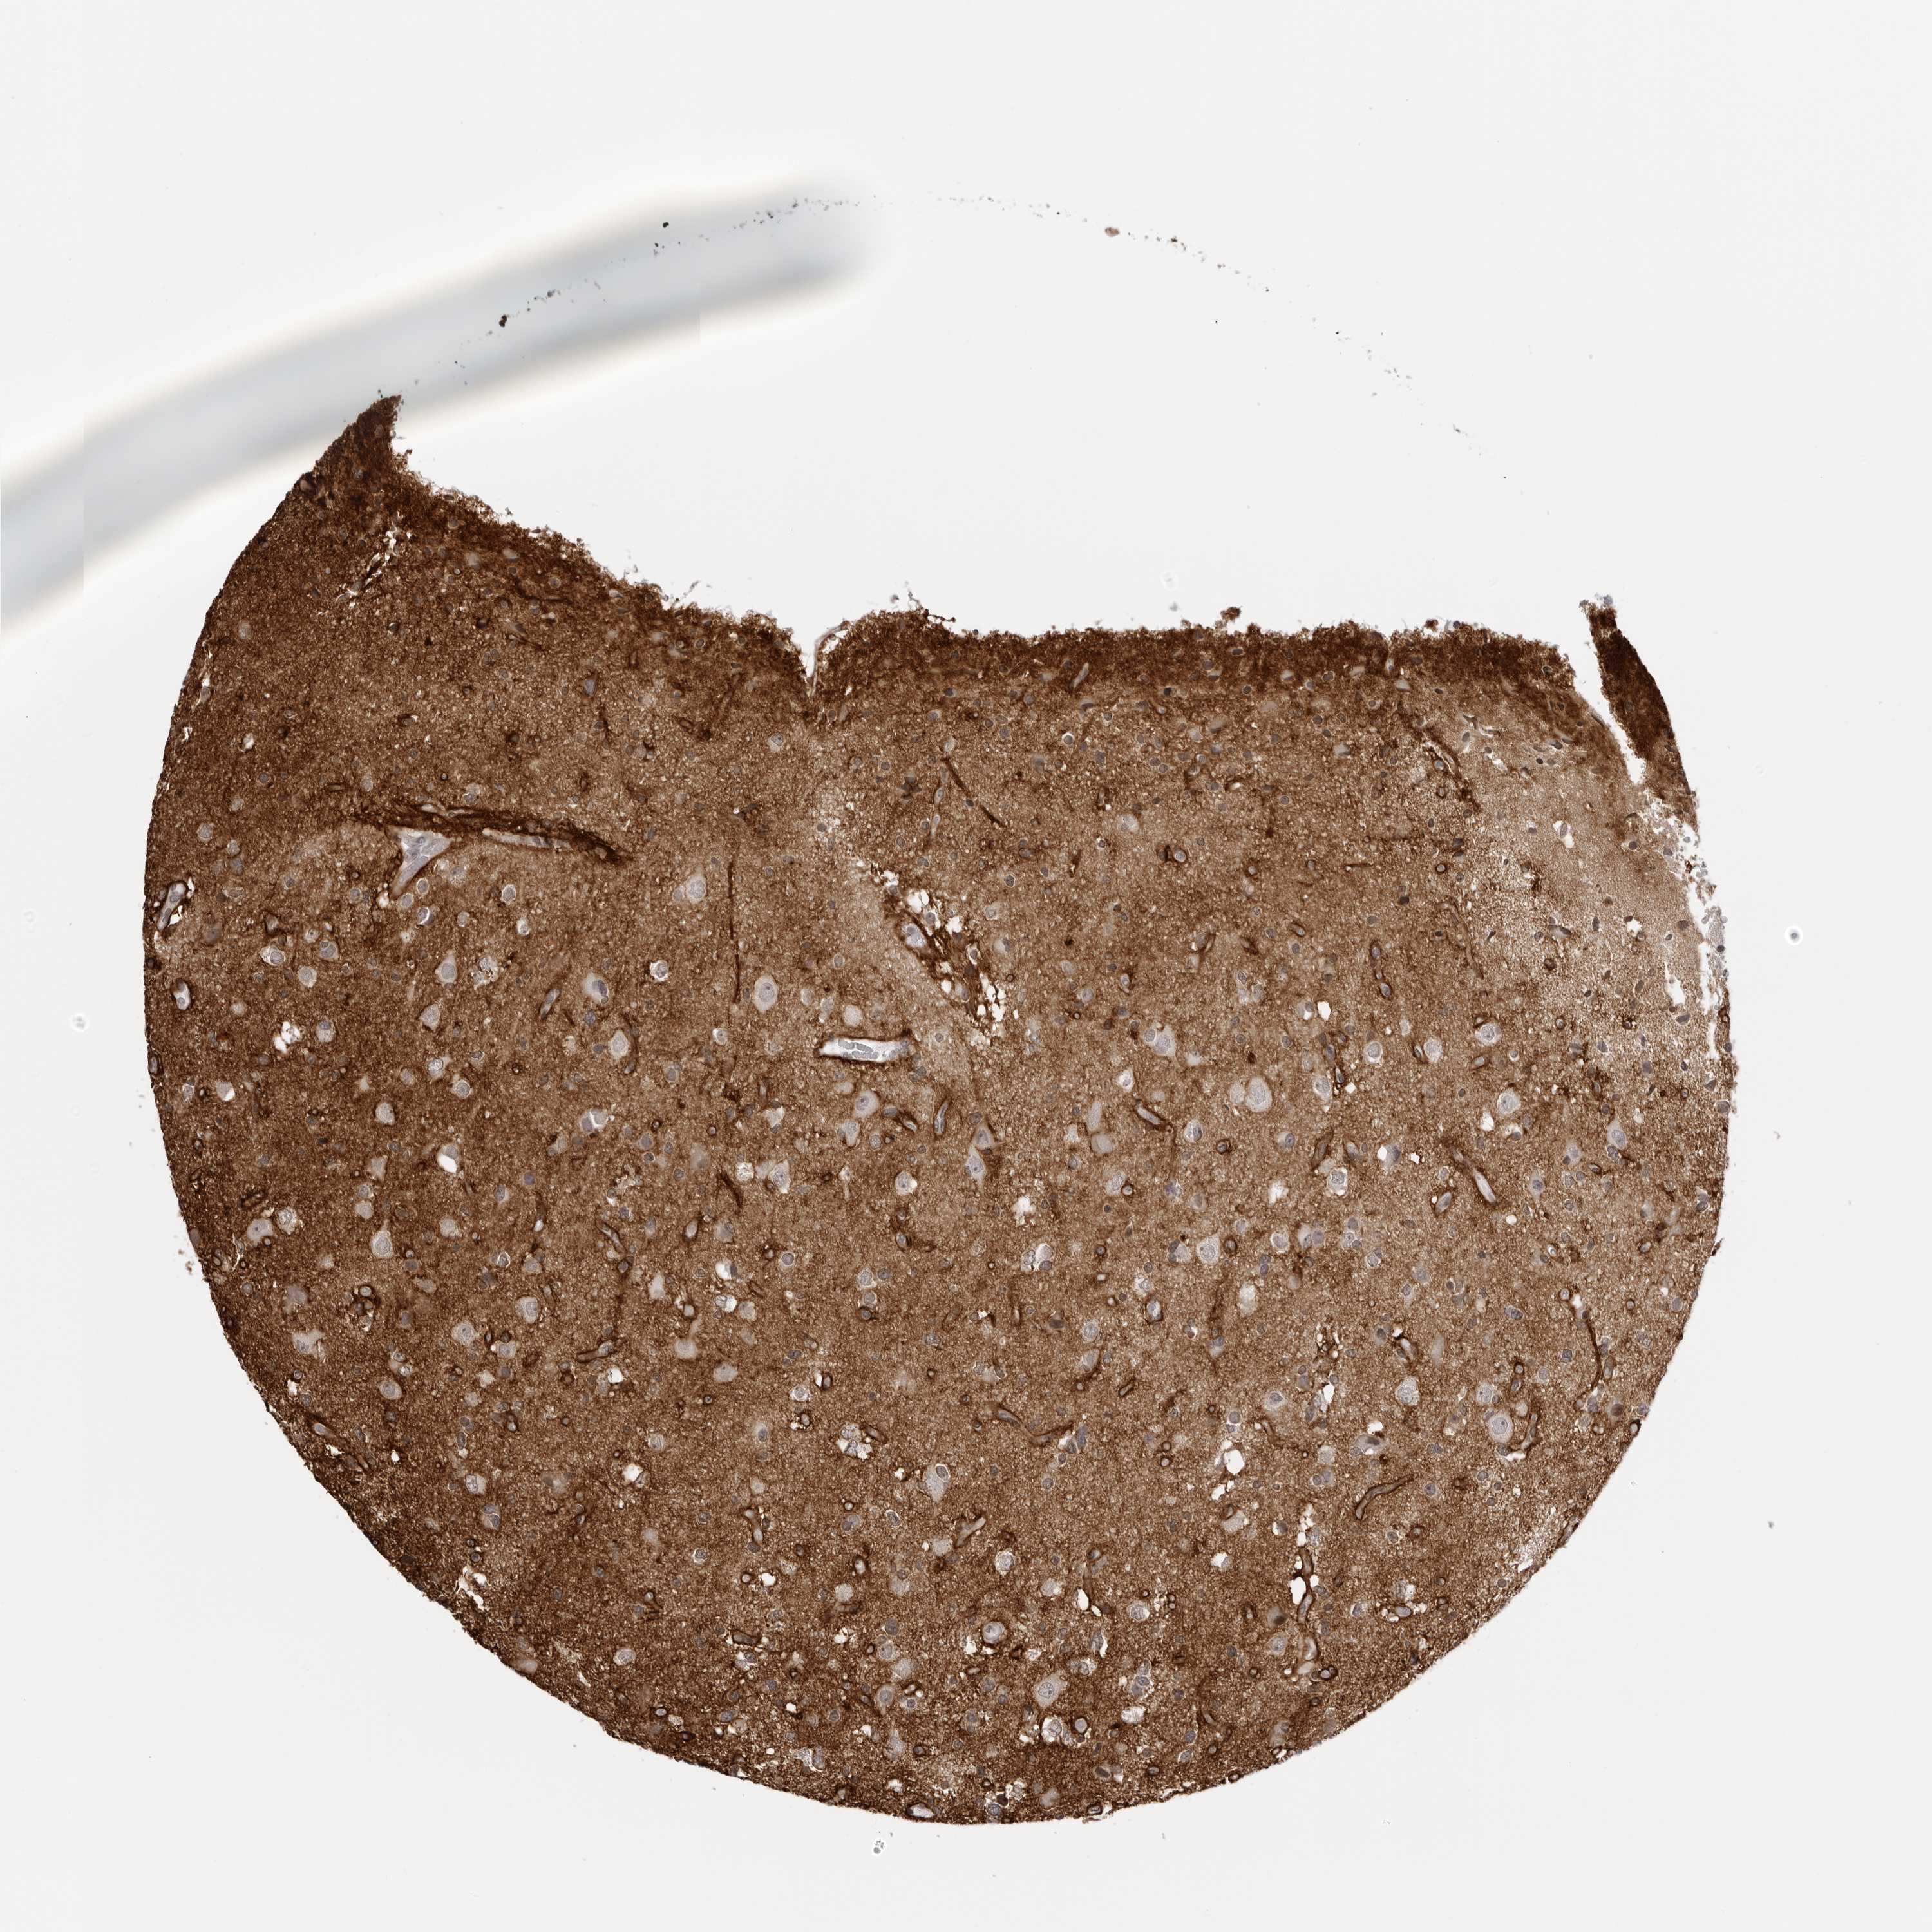

GLIOMA - Protein expressioni

A mouse-over function shows sample information and annotation data. Click on an image to view it in a full screen mode. Samples can be filtered based on level of antibody staining by selecting one or several of the following categories: high, medium, low and not detected. The assay and annotation is described here.

Note that samples used for immunohistochemistry by the Human Protein Atlas do not correspond to samples in the TCGA dataset.

Antibody stainingi

Antibody staining in the annotated cell types in the current human tissue is reported as not detected, low, medium, or high, based on conventional immunohistochemistry profiling in selected tissues. This score is based on the combination of the staining intensity and fraction of stained cells.

Each image is clickable and will lead to virtual microscopy that enables deeper exploration of all samples and also displays staining intensity scores, fraction scores and subcellular localization as well as patient and tissue information for each sample.

Antibody HPA028411

Staining

High

Medium

Low

Not detected

Intensity

Strong

Moderate

Weak

Negative

Quantity

>75%

75%-25%

<25%

None

Location

Nuclear

Cytoplasmic/membranous

Cytoplasmic/membranous,nuclear

Glioma, malignant, High grade

Glioma, malignant, Low grade